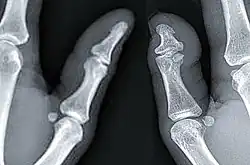

| X-ray of a regular thumb (left) and a thumb with brachydactyly type D (right) showing distal phalange brachyphalangy of said thumb. | |

Brachydactyly type D is a skeletal condition that exhibits a “partial fusion or premature closing of the epiphysis with the distal phalanx of the thumb,” according to Goodman et alia (1965).[6] J.K. Breitenbecher (1923) found that the distal phalanges of short thumbs were one-half the length of full-length thumbs, while R.M. Stecher (1957) claimed that it is approximately two-thirds. The condition may be unilateral (affecting one thumb) or bilateral (affecting both).[6]